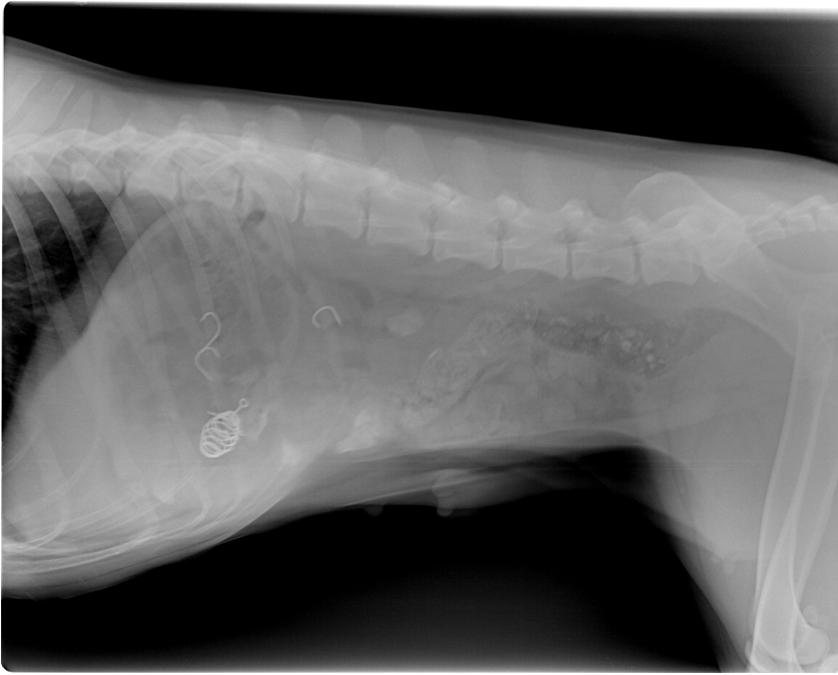

经我院医师详细检查后并拍摄CR后确诊苏格胃肠道内有鱼钩样高密度阴影。建议手术取出。经主人同意后,行肠切开术并进行腹膜腔灌洗。共从苏格肠道内取出7颗鱼钩,其中包括一颗爆炸钩。现苏格已经拆线且精神食欲恢复正常。

CR图像